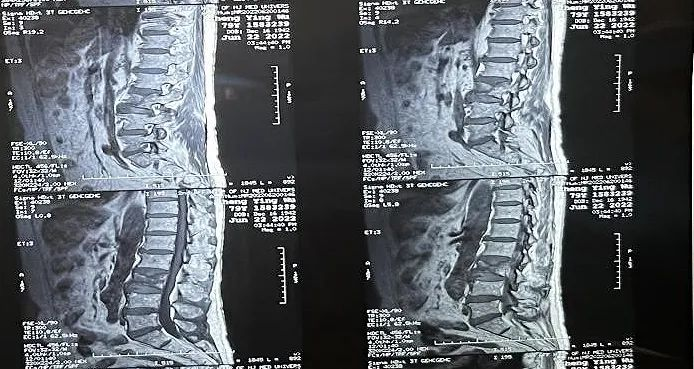

臨床手術(shù)過程

術(shù)中切口5毫米,在大平板C臂機的透視指引下,確定了進針的方向及進針的深度。經(jīng)椎弓根向椎體置管,建立通道,插入骨擴張器(球囊)。球囊擴張恢復(fù)椎體高度,并在椎體內(nèi)形成空腔,確定骨水泥的注入劑量,并注入骨水泥觀察其擴散情況。